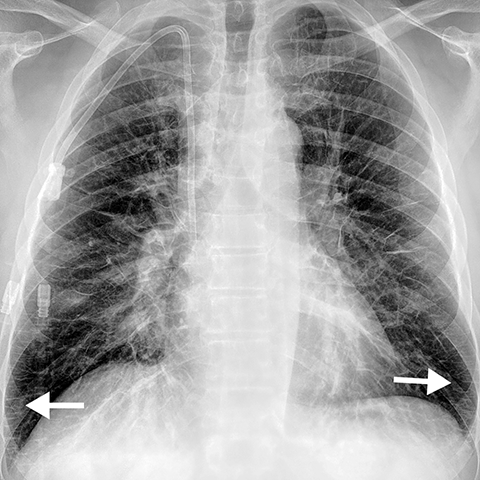

Chest Pain